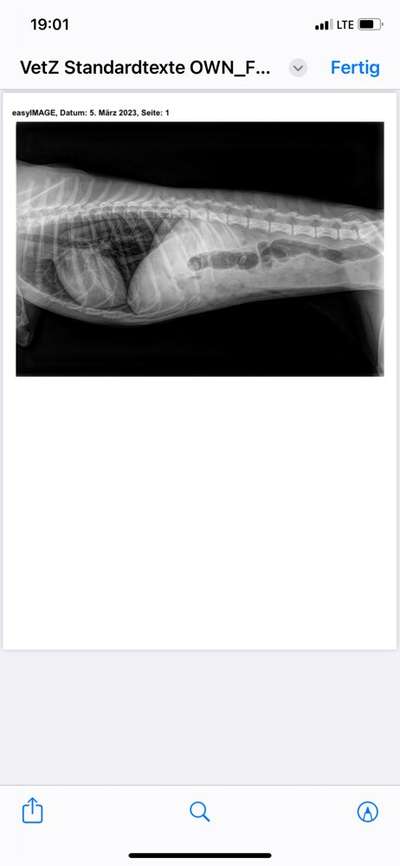

Wie sind dann heute noch in die Tierklinik gefahren weil das Erbrechen nicht aufhörte, die Nahrung Verweigererte und sie nichts bei sich behielt.

Dort haben sie ein Röntgenbild gemacht, eine Spritze gegen Übelkeit gegeben und uns eine weiße Paste zum ins Maul spritzen mitgegeben. Das Zeug soll wohl eine Schutzschicht um Magen und Darmwand legen.

Der Arzt meinte dass ihr Magen und ihr Darm entzündet sind und das kann nicht allein von den giardien kommen.

Anbei das Bild. Vielleicht habt ihr ja eine Einschätzung was man da sieht.